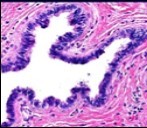

Cutaneous ciliated cyst is layered with a singular layer of ciliated epithelial cells which are chiefly constituted by cuboidal to columnar epithelium, traversed by partially configured fibrous tissue septa with an admixture of randomly dispersed, intraluminal papillary projections akin to those cogitated in the fallopian tube. Superimposed epithelium is inundated with well vascularized, parallel bundles of collagen although smooth muscle is absent 7, 8.

Cystic structures cogitated within deep dermal or subcutaneous tissue can be impacted with haemorrhagic fluid. Cyst lining is smooth, regular and is essentially composed of a singular layer of columnar epithelium with focally pseudostratified columnar epithelium, a circumscription of loosely configured, well vascularized, fibroconnective or fibrocollagenous tissue and an absence of inflammatory infiltrate.

Alternatively, cutaneous ciliated cyst can be lined by non ciliated cuboidal or columnar epithelium with intermingled intercalated, dark or round peg cells. Foci of squamous metaplasia can be occasionally exemplified in the adherent epithelium whereas mucinous cells or apocrine-like features are exceptional 6, 8. Figure 1, Figure 2, Figure 3, Figure 4, Figure 5, Figure 6, Figure 7, Figure 8, Figure 9, Figure 10, Figure 11, Figure 12. 11, 12, 13, 14, 15, 16, 17, 18, 19.

Figure 7.Cutaneous ciliated cyst with papillary structures, a coating of ciliated columnar epithelium supported by a connective tissue framework (15).